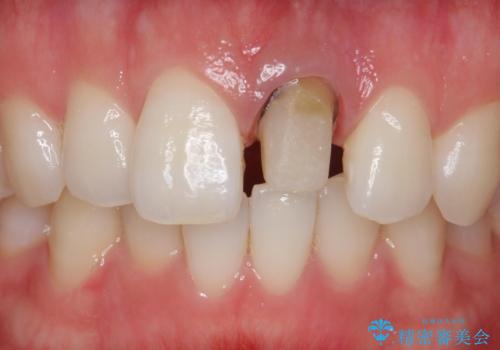

- 前歯の変色を主訴に来院された患者様です。

より審美的な修復を行いたいとのことであったため、ジルコニアクラウンでの修復を行います。

- 左上1 : 仮歯 / 11,000円、ジルコニアクラウン(スペシャル) / 154,000円 合計165,000円(税込)費用は治療当時の料金となります